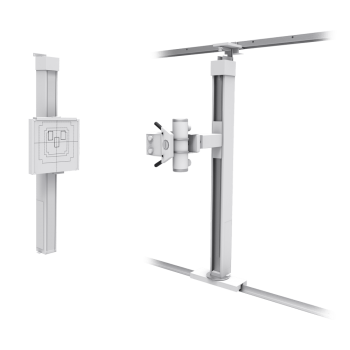

Expansive Movement

Featuring a floor-to-wall, floor-to-ceiling tube stand and a compact wall stand, the system delivers extensive vertical travel allowing for a full range of upright positions. The tube stand features electromagnetic brakes and a fixed positioned tube arm for easy and accurate positioning to the wall stand.

Compact Wall Stand

The ultra-compact VS100 upright is powered by an electric lock release handle and dual counterweight cables for added patient and user safety. Its expansive vertical travel of 58.4 in (148.3 cm) enables a complete range of exams from skull to weight-bearing knee and ankle exams.’